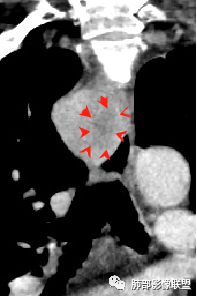

2.定位:右后上纵隔肿块,与食管关系密切,边缘光滑,冠状位显示肿块与食管壁结构相顺延,上下径大于横径,呈现跨管壁内外生长倾向,食管管腔狭窄,而气管腔内未见突入,因此食管来源肿块可能大。

3.结合CT增强图像及食道钡餐影像(管壁整体柔软,粘膜线完整),提示肿块来源于粘膜下。

肿块影边界清楚、局限,未见管壁及周边浸润,提示良性病灶。